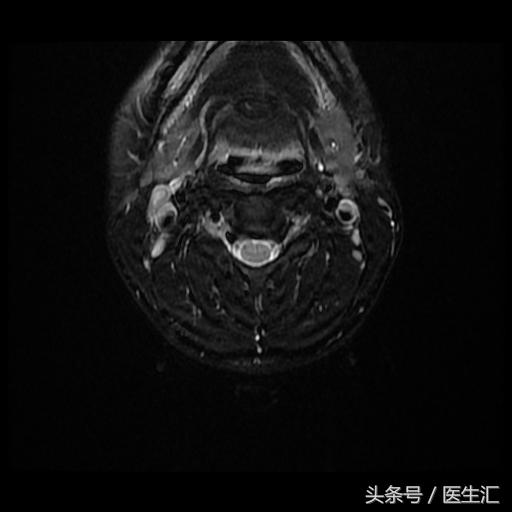

颈MRI:长节段髓内病变(前角)(见图13、14、15、16)

头颅MRI:(见图17)

专家判读:小脑中脚、苍白球、白质、胼胝体皆有病变。